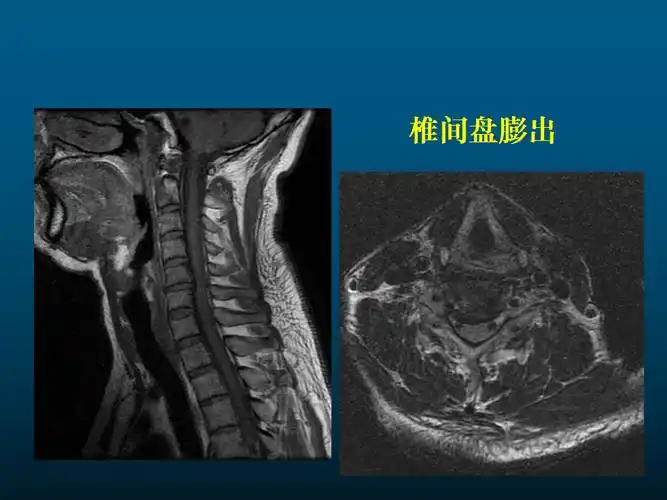

颈椎间盘突出征核磁共振矢状位(mri)

见习脊柱,五官mrippt

一篇课件详解颈椎病的mri诊断技巧